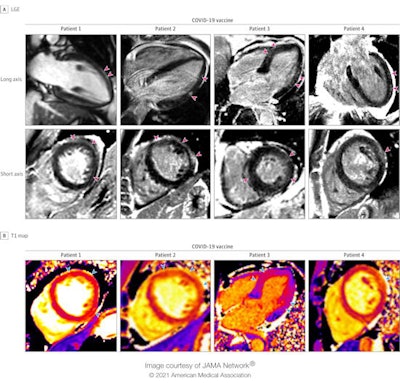

Cardiac MRI scans of patients with acute myocarditis following COVID-19 vaccination. Late gadolinium enhancement (LGE) images and T1 maps are shown in four patients who recently received a COVID-19 vaccine. Patients 1, 2, and 4 demonstrate epicardial LGE, and patient 3 demonstrates patchy, diffuse LGE (pink arrowheads), which are consistent with myocarditis. T1 maps demonstrate abnormal (elevated) native T1 in the regions with late gadolinium enhancement (blue arrowheads). Image and caption courtesy of JAMA Cardiology.Although a causal relationship between the COVID-19 vaccine and acute myocarditis in these patients can't be definitively established, there appeared to be no other obvious reason for the injury, Kim and colleagues noted.

The four included three men between the ages of 23 and 36 and a 70-year-old woman, and all of whom presented to the hospital with severe chest pain and biomarker evidence of myocardial injury. Their cardiac MRI findings were typical for myocarditis; all were hospitalized, underwent treatment for the condition, and were released within two to four days.

The group's study cohort consisted of seven individuals diagnosed with acute myocarditis on cardiovascular MRI between February and April of 2021. Of the seven, four developed the condition within five days of receiving an mRNA COVID-19 vaccine; all four had received a second dose (two had Moderna and two had Pfizer).